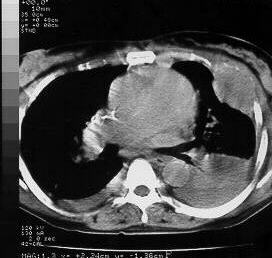

Chest CTs demonstrating the left thoracic wall mass, with intra-thoracic involvement, and costal arch destruction.